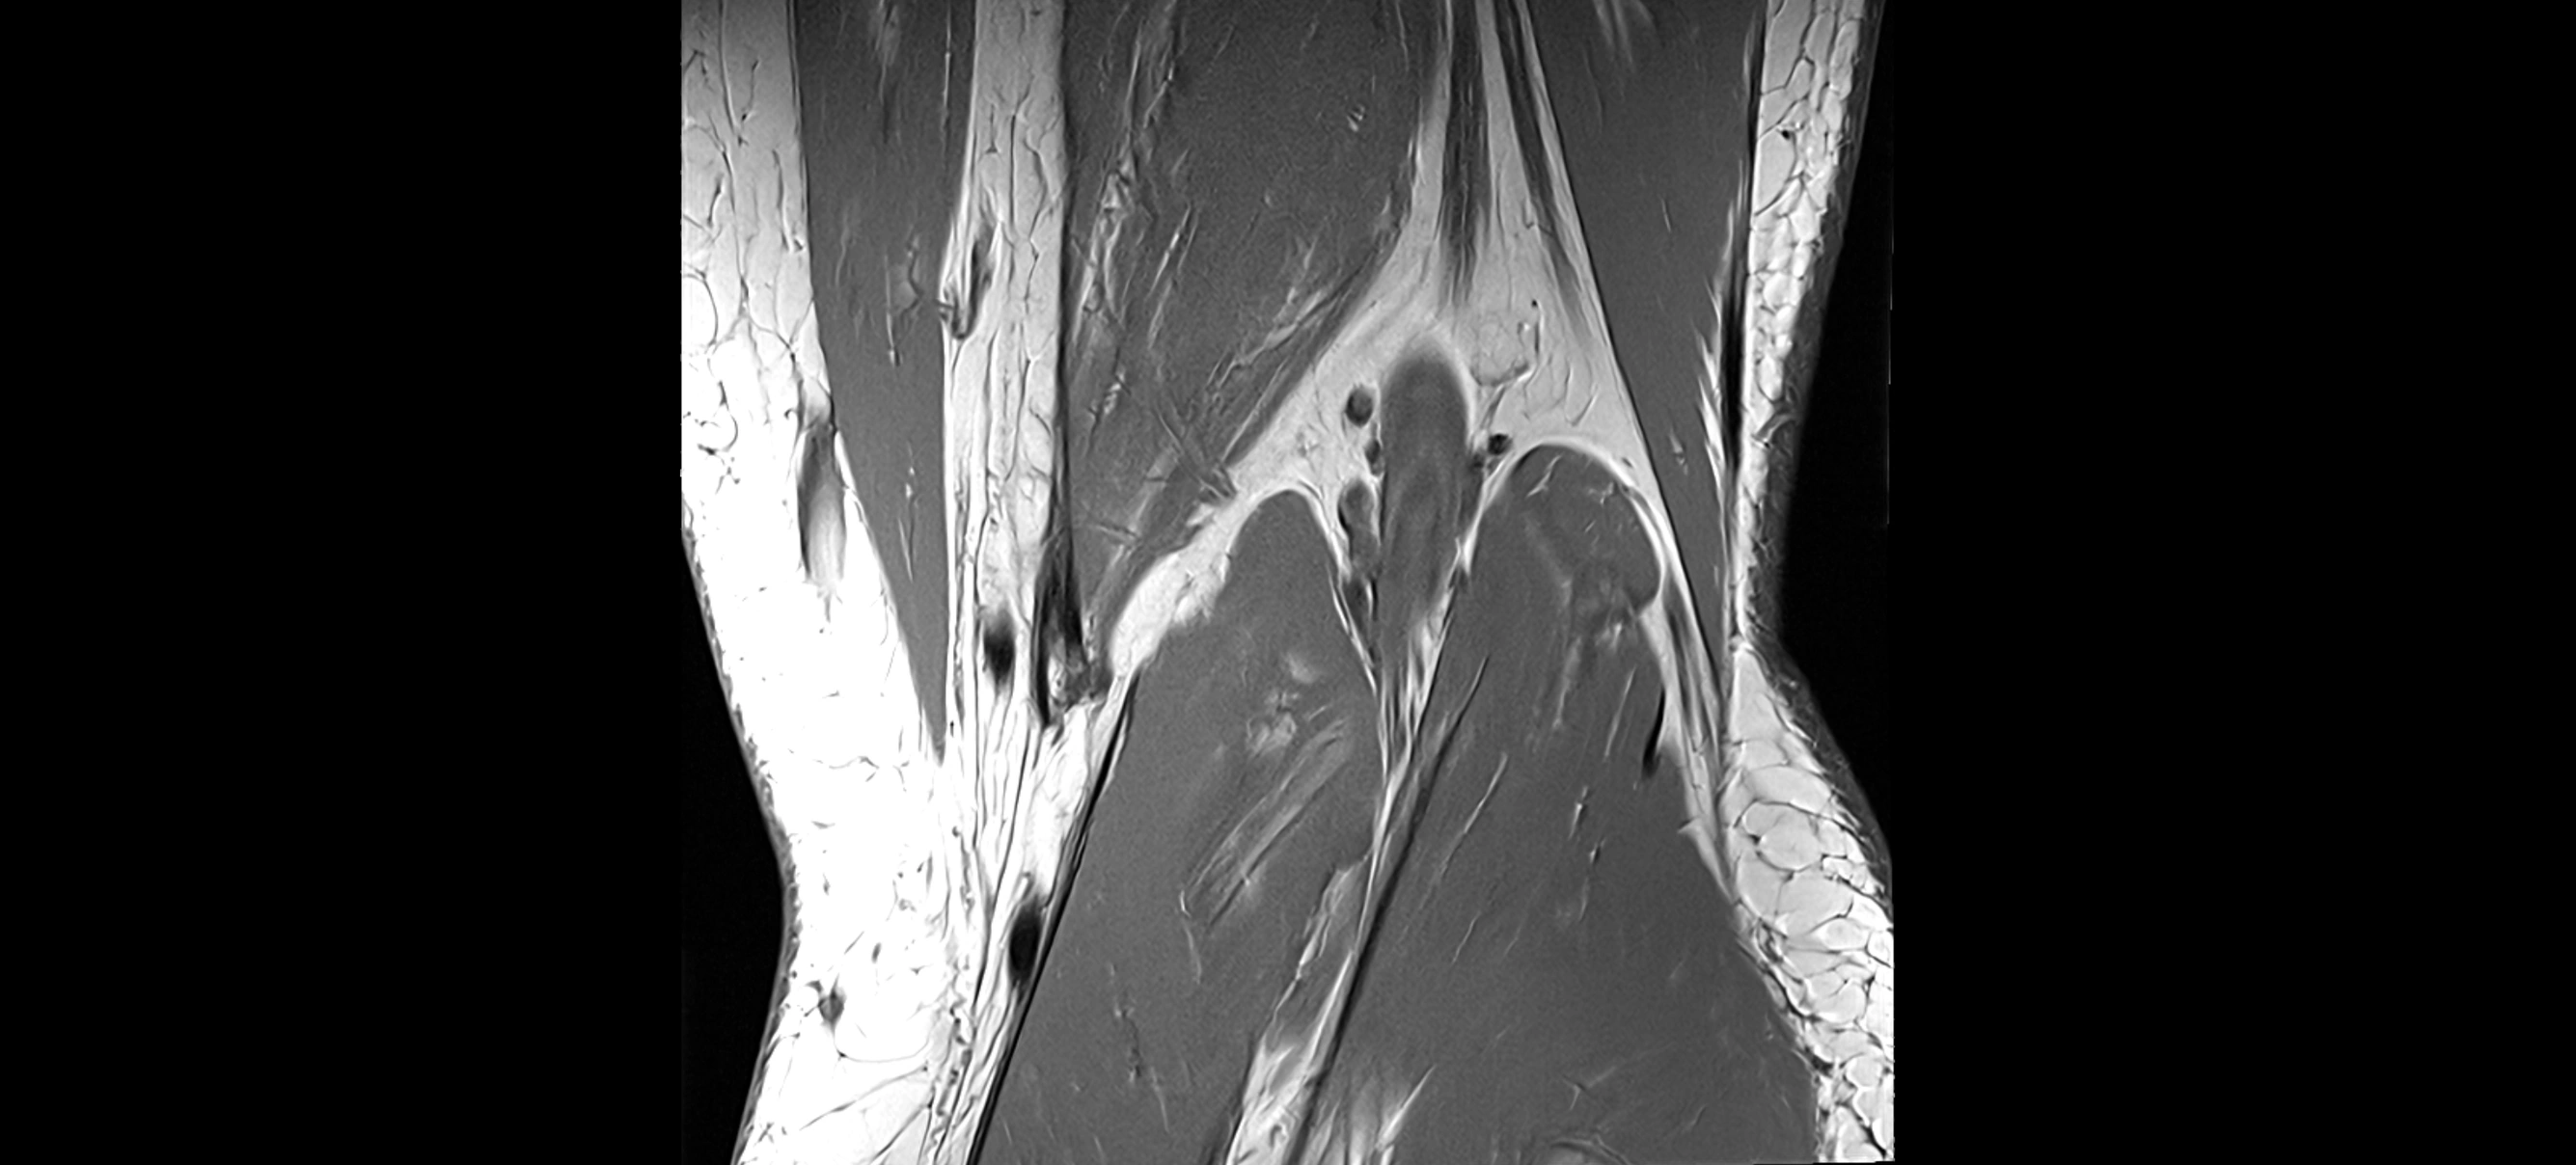

MRI images

image